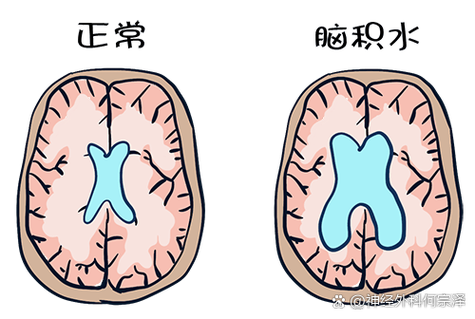

脑积水是由于脑脊液循环通路发生阻塞,导致脑脊液在脑室系统内过多积聚,使脑室扩大,从而压迫周围正常的脑组织,脑积水的症状发展通常比较缓慢,呈进行性加重,但急性脑积水(如脑出血后突然阻塞)则发展迅速。

脑积水的症状主要与颅内压增高和脑组织受压有关,具体表现因发病年龄和病情急缓而异。